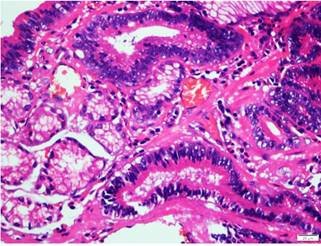

Se envió la muestra para el estudio histopatológico. El resultado de la patología fue reportado de la siguiente manera: “Resección endoscópica de la lesión (pared gástrica) con adenocarcinoma gástrico temprano (precoz, superficial, bien diferenciado) de variedad intestinal que compromete hasta la muscular de la mucosa sin traspasarla. Líneas de sección laterales y borde medial alejados y libres de lesión” (Figuras 5 y 6).